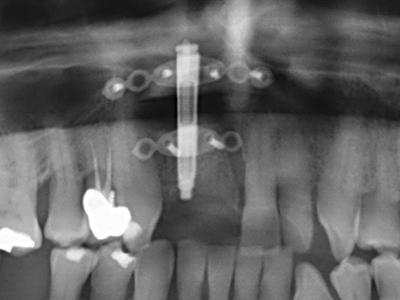

Fig. 11: El ortopantomograma posoperatorio presenta el aumento vertical y la elevación del suelo del seno.

Fig. 12: Después de seis meses de cicatrización se muestra una cresta maxilar vital con unas dimensiones suficientes en todas las direcciones.

Otras indicaciones

Fig. 25: Ortopantomograma después de alcanzar la altura de distracción final, antes del período de consolidación.

Fig. 26: Después de una fase de consolidación de cuatro meses, se observan condiciones estables antes de insertar el implante.